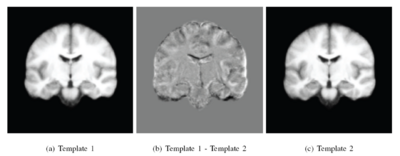

The following figure shows the difference images between the three templates shown above.

The following figure shows the three robust templates computed by iCluster.